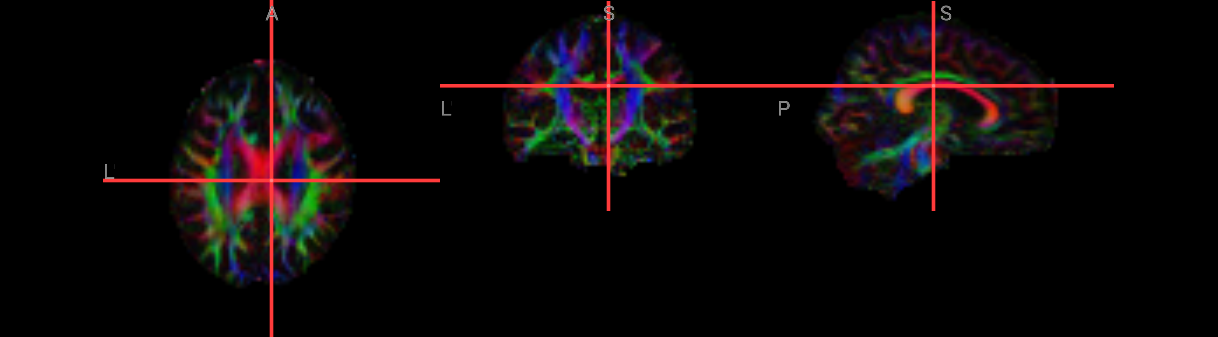

When it is done, load the files dti_V1 and dti_FA in fsleyes. With the file dti_V1 highlighted, click on the “Modulate by” menu and select dti_FA. This will create an image that shows the primary direction of diffusion at each voxel, with red representing diffusion that is primarily left to right, green representing back to forward, and blue representing bottom to top. If the tensors were fit correctly, you should see mostly red in the corpus callosum and blue in the corona radiata, since those fiber bundles are mostly restricted to the left to right and bottom to top directions.

# Load FA map

fa_nii = nib.load("./FA/dti_FA_FA.nii.gz")

fa_data = fa_nii.get_fdata()

# Load V1 map

v1_nii = nib.load("../dti_V1.nii.gz")

v1_data = v1_nii.get_fdata() # shape = (X, Y, Z, 3)

# Scale eigenvectors by FA to get color FA map (DEC map)

dec_data = np.abs(v1_data) * fa_data[..., None]

# Prepare header and save new image

hdr = v1_nii.header.copy()

hdr.set_intent("vector")

hdr["intent_name"] = b"RGB"

dec_nii = nib.Nifti1Image(dec_data.astype(np.float32), v1_nii.affine, header=hdr)

nib.save(dec_nii, "./FA/dti_DEC.nii.gz")

nv = NiiVue()

nv.load_volumes([{"path": './FA/dti_DEC.nii.gz'},

])

nv

Image(url='https://raw.githubusercontent.com/NeuroDesk/example-notebooks/refs/heads/main/books/images/tbss_dti_DEC.png')